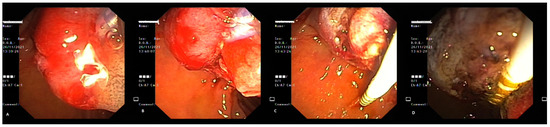

3. Case Report 2

4. Case Report 3